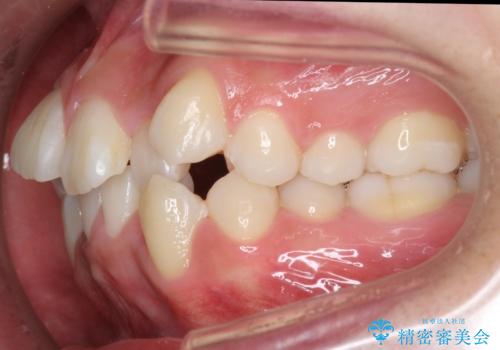

八重歯 抜かずにマウスピース矯正治療

- 八重歯を主訴に来院。

(1)口元を下げるなら、上下左右抜歯でワイヤー矯正

(2)奥歯を後ろに下げ、歯並びを拡大し、歯を少し削って抜かずにインビザライン矯正 矯正用ミニスクリュー併用 口元は下がらない

の選択肢から選んでもらいました。

目立たない装置希望とのことで、(2)を選択されました。

抜歯をしていないので口元は変わっていません。

八重歯も重症でなければインビザラインでも並びを歯を抜かずに整えることができます。